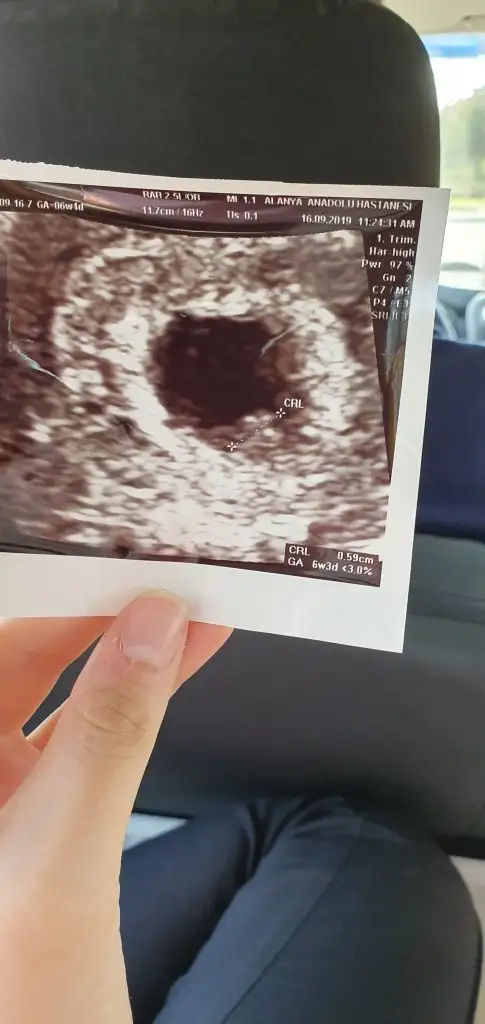

Buna göre kızEki Görüntüle 2309620 Bana da yorum yapar mısınız acabavajinal ultrason

6 yada 7 hafta olmalı